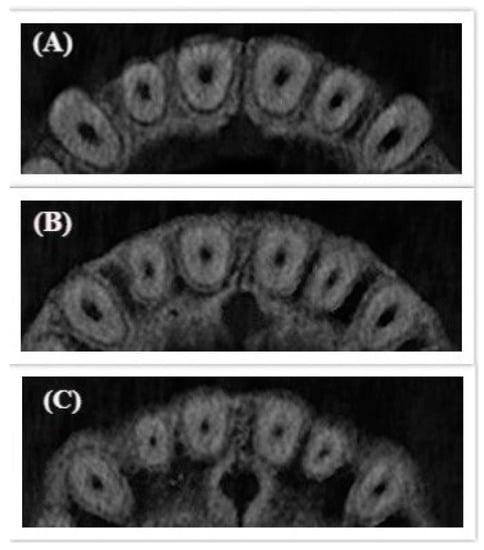

For mandibular anterior teeth, the cross-sectional root canal shape was defined to be oval or long oval for incisors in the three thirds in 95% at the young age. In 5%, the cross-sectional root canal shape was changed in the middle third to ribbon type I and in the apex re-changed to long-oval. For canines, the shape of the root canal was defined to be oval in three thirds in 96%. In 4%, the root canal shape changed in the middle third (Figure 2).

Figure 2.

Changed cross-sectional root canal shape for mandibular anterior teeth in the middle third. (A) Coronal; (B) Middle; (C) Apical.